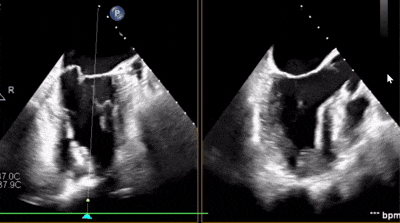

術(shù)后超聲

反流變?yōu)檩p度,反流等級(jí)從4+降為1+;

術(shù)后平均跨瓣壓差1mmHg;

夾子夾合量:前葉15mm,后葉10mm;

剩余瓣環(huán)面積:術(shù)后有效瓣環(huán)面積3.7cm²;

二尖瓣3區(qū)可見(jiàn)夾子強(qiáng)回聲,位置固定。

術(shù)前術(shù)后對(duì)比

術(shù)后